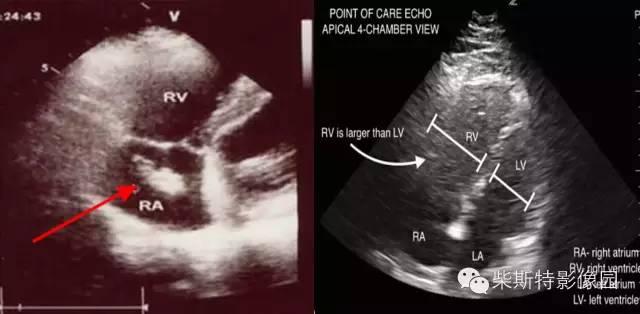

5. 超声心动图

超声心动图可提示诊断、对 PTE 进行分层以及除外其他心血管疾病,并因可床旁进行检查,操作性强,重要性日益受到重视。超声心动图表现包括直接征象和间接征象(表 6)。

图 6. 超声征象(来源:Echocardiography in the Evaluation of Pulmonary Embolism.Cardiol Rev)

图 7. 超声征象(来源:Echocardiography in the Evaluation of Pulmonary Embolism.Cardiol Rev)

当疑似 PTE 患者的超声心动图出现以上表现时,需警惕存在 PTE。

Kurzyna 等的研究结果表明,单独应用 60~60 征、McConnell‘s 征在识别急性肺栓塞方面的敏感性分别为 25% 和 19%、特异性分别为 94% 和 100%。两者联合应用时可提高急性肺栓塞检出率(敏感性 36%、特异性 94%)。

心脏彩超